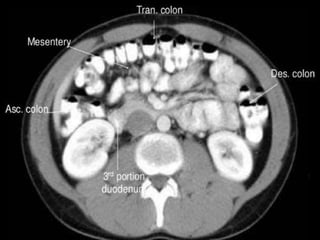

CT cross sectional anatomy.

CT – computedtomography. •Cross-sectional modality with capabilities for multiplanar reconstruction and dynamic imaging to assess vascularity •Tube rotates around the body and a circle of stationary detectors detects the penetrating x-rays forming an image.